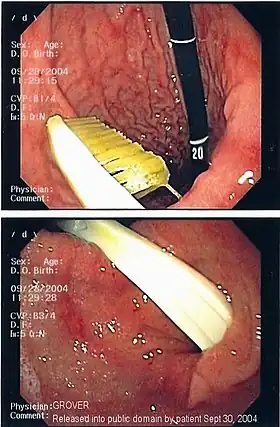

Commonly swallowed objects include coins, buttons, batteries, and small bones (such as fish bones),[1] but can include more complex objects, such as eyeglasses,[5] spoons,[6] and toothbrushes[5] (see image).

Endoscopic retrieval involves the use of a gastroscope or an optic fiber charge-coupled device camera. This instrument is shaped as a long tube, which is inserted through the mouth into the esophagus and stomach to identify the foreign body or bodies. This procedure is typically performed under conscious sedation. Many techniques have been described to remove foreign bodies from the stomach and esophagus. Usually the esophagus is protected with an overtube (a plastic tube of varying length), through which the gastroscope and retrieved objects are passed.[11]

Once the foreign body has been identified with the gastroscope, various devices can be passed through the gastroscope to grasp or manipulate the foreign body. Devices used include forceps, which come in varying shapes, sizes and grips,[12] snares, and oval loops that can be retracted from outside the gastroscope to lasso objects,[13] as well as Roth baskets (mesh nets that can be closed to trap small objects),[14] and magnets placed at the end of the scope or at the end of orogastric tubes.[12][15] Some techniques have been described that use foley catheters to trap objects, or use two snares to orient foreign bodies.[6]